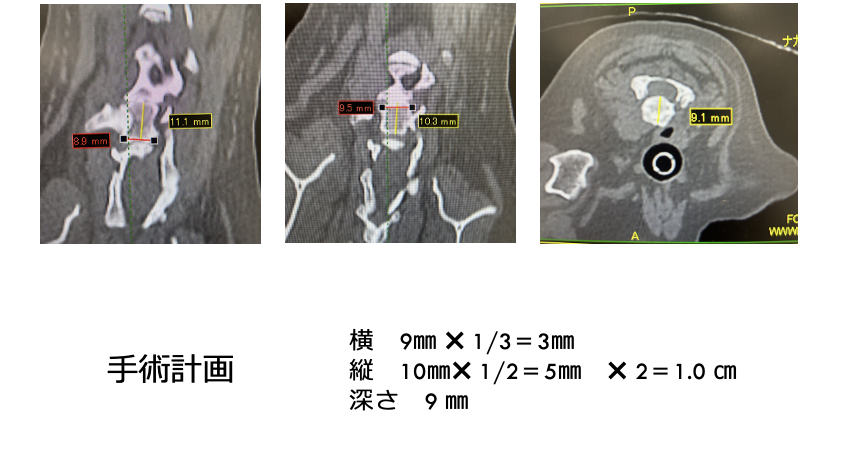

左前肢破行、後肢ふらつきを主訴に来院しました。CT・MRI撮影より、C5-6の椎間板ヘルニア、小脳背側のくも膜下嚢胞が認められました。症状が軽度から中等度、また小脳背側にくも膜下嚢胞が認められ麻酔のリスクなどを考慮し、まずは内科療法から行いました。2か月後症状の改善が認められず、症状も進行し、起立・歩行困難となりました。

左前肢破行、後肢ふらつきを主訴に来院しました。CT・MRI撮影より、C5-6の椎間板ヘルニア、小脳背側のくも膜下嚢胞が認められました。症状が軽度から中等度、また小脳背側にくも膜下嚢胞が認められ麻酔のリスクなどを考慮し、まずは内科療法から行いました。2か月後症状の改善が認められず、症状も進行し、起立・歩行困難となりました。

C5-6椎間板ヘルニア、くも膜下嚢胞と診断した